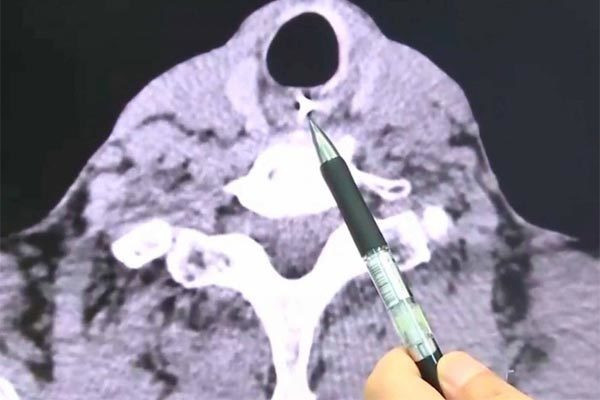

Kết quả chụp cắt lớp vi tính cho thấy, phần răng giả rơi ra đã xâm nhập vào thực quản của ông Zhu. Đáng nói, các răng giả có rất nhiều móc sắt khiến chúng móc chặt vào cổ họng ông.